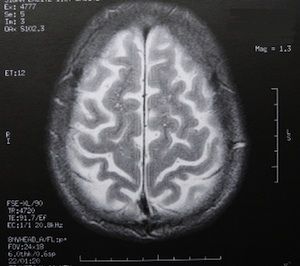

Sie sind hier: Startseite Nachrichten Gesundheit Japanische Forscher halten einen kleinen Gleichgewichtstest für ziemlich aussagekräftig Bild: pixelio.de/Dieter Schütz